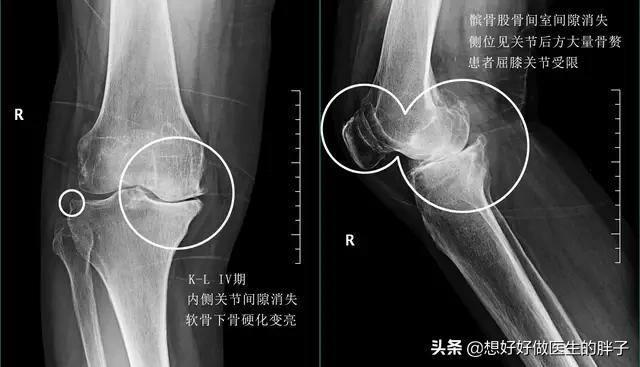

●中期的骨关节炎,关节内的软骨磨损会越来越严重,关节会出现积液,会出现明显的疼痛,有一些患者在屈伸关节的时候已经会出现轻度的受限。X线上我们可以看到轻度的关节间隙狭窄,可以看到比较大量的骨赘形成。

●晚期的骨关节炎,关节间隙已经发生了明显的狭窄关节活动角度以及功能都会有明显的问题,患者往往会出现特别严重的疼痛,平时休息的时候和夜间睡眠的时候也会出现疼痛。这个阶段往往进行关节肌肉的强化锻炼,患者是无法接受的,所以建议坚持三个基础的康复锻炼就可以了,如果症状比较明显难以忍受,对生活质量影响特别大,建议要考虑关节置换治疗。想要通过运动强化关节功能的话,游泳是非常好的选择,即使仅仅在水里行走,由于浮力的作用,关节腔受到的压力也会变得最小。